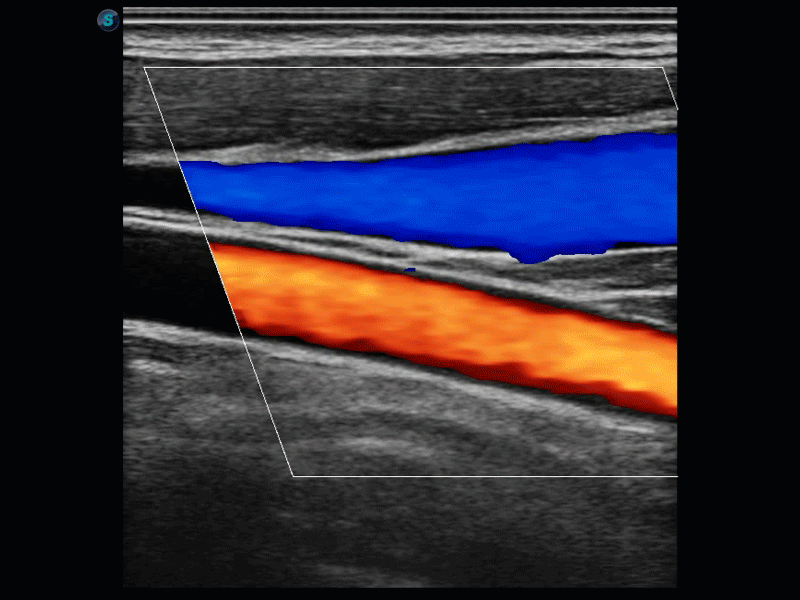

開立醫(yī)療通過不斷的技術(shù)創(chuàng)新,為大眾的生命健康提供持續(xù)關(guān)愛。P12 Plus采用全新一代超聲成像平臺,新平臺旨在將真實(shí)還原組織解剖結(jié)構(gòu)作為首要目標(biāo)。平臺采用全新集成化硬件模塊,搭載新一代芯片,系統(tǒng)性能得到大幅提升,為您的診斷提供了豐富的臨床信息。優(yōu)異的圖像表現(xiàn),豐富的探頭配置,全面的應(yīng)用功能,為您日常診斷提供了可靠的助手。

彩色多普勒超聲診斷系統(tǒng)